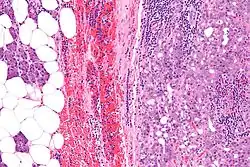

![]() | |

| Micrograph of an acinic cell carcinoma (right of image) and acinar glands (parotid gland - left of image). H&E stain. | |